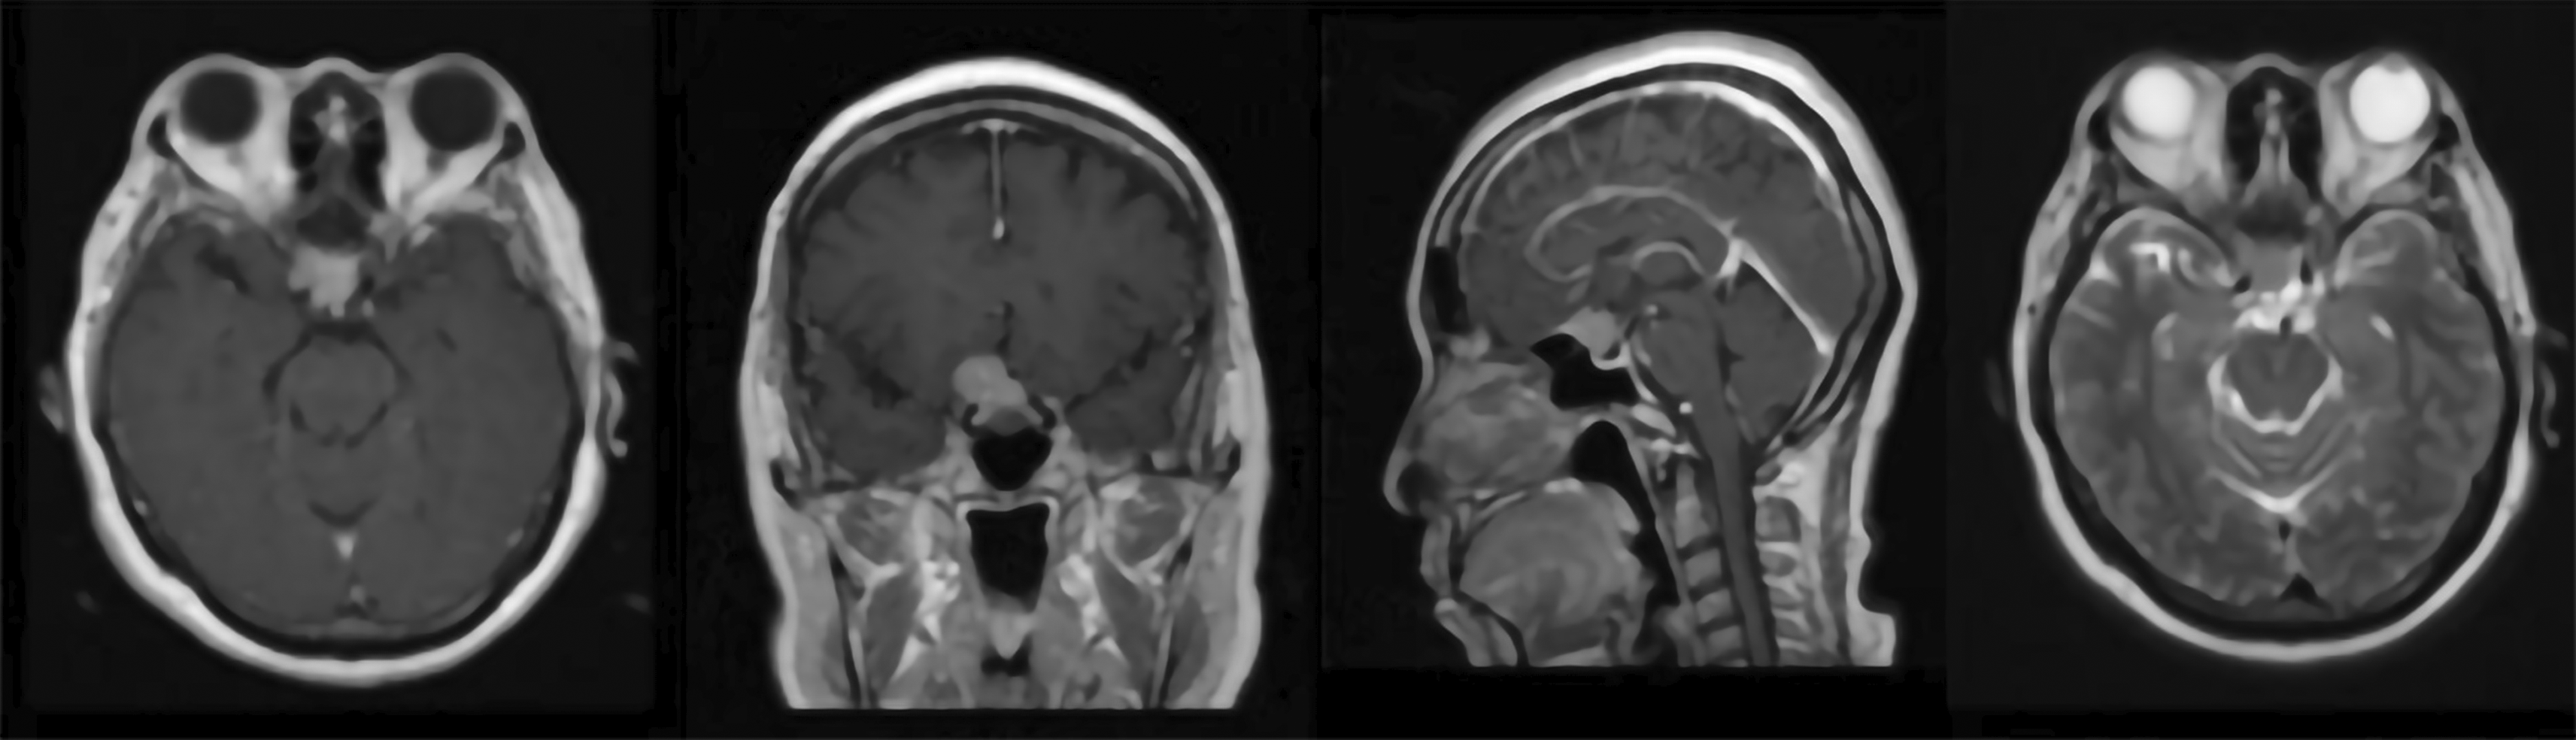

A 54-year-old female presented with a two-month history of progressively blurred vision and a right temporal hemianopia, superimposed on a two-year history of chronic headaches. Her medical history was negative for arterial hypertension, bleeding disorders or anticoagulant use. The timeline of the case presentation is shown in Figure 1. Hormonal status was within normal limit. Preoperative magnetic resonance imaging (MRI) revealed a 1.91 × 2.01 × 1.82 cm solid, globular mass that avidly enhanced with gadolinium and showed a dural tail attached to the tuberculum sella ( Figure 2). She underwent a Simpson Grade I resection of the tumour via a endoscopic endonasal transsphenoidal approach ( Figure 3). The surgery was unremarkable and histopathology confirmed a Meningothelial Meningioma, WHO Grade I. The immediate postoperative period (days one to four) was uneventful; the patient was conscious and alert with improving vision. The patient showed minimal CSF leakage from the nostril postoperatively and some polyuria adequately manage with desmopressin tablet 0.1 mg. However, on the postoperative day five, the patient was found to be drowsy (Glasgow Coma Scale score of 13).

T2 weighted image showed isointense mass at tuberculum without any remarkable surrounding oedema.